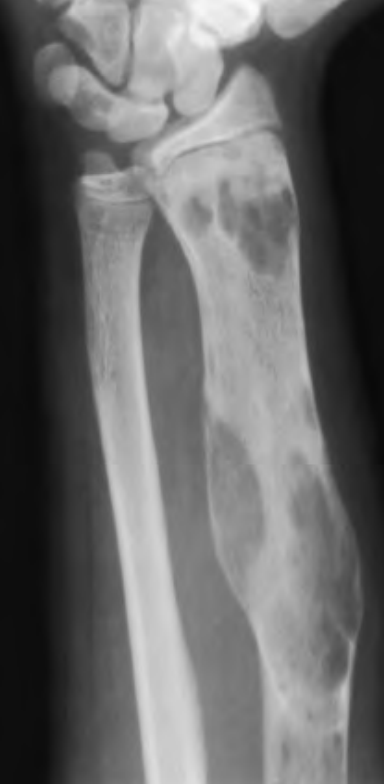

descrever e dar diagnóstico mais provável e diferenciais.

Lesão lítica alongada, com aspecto em “vidro fosco”, zona de transição curta, focos de esclerose, localizada em osso longo